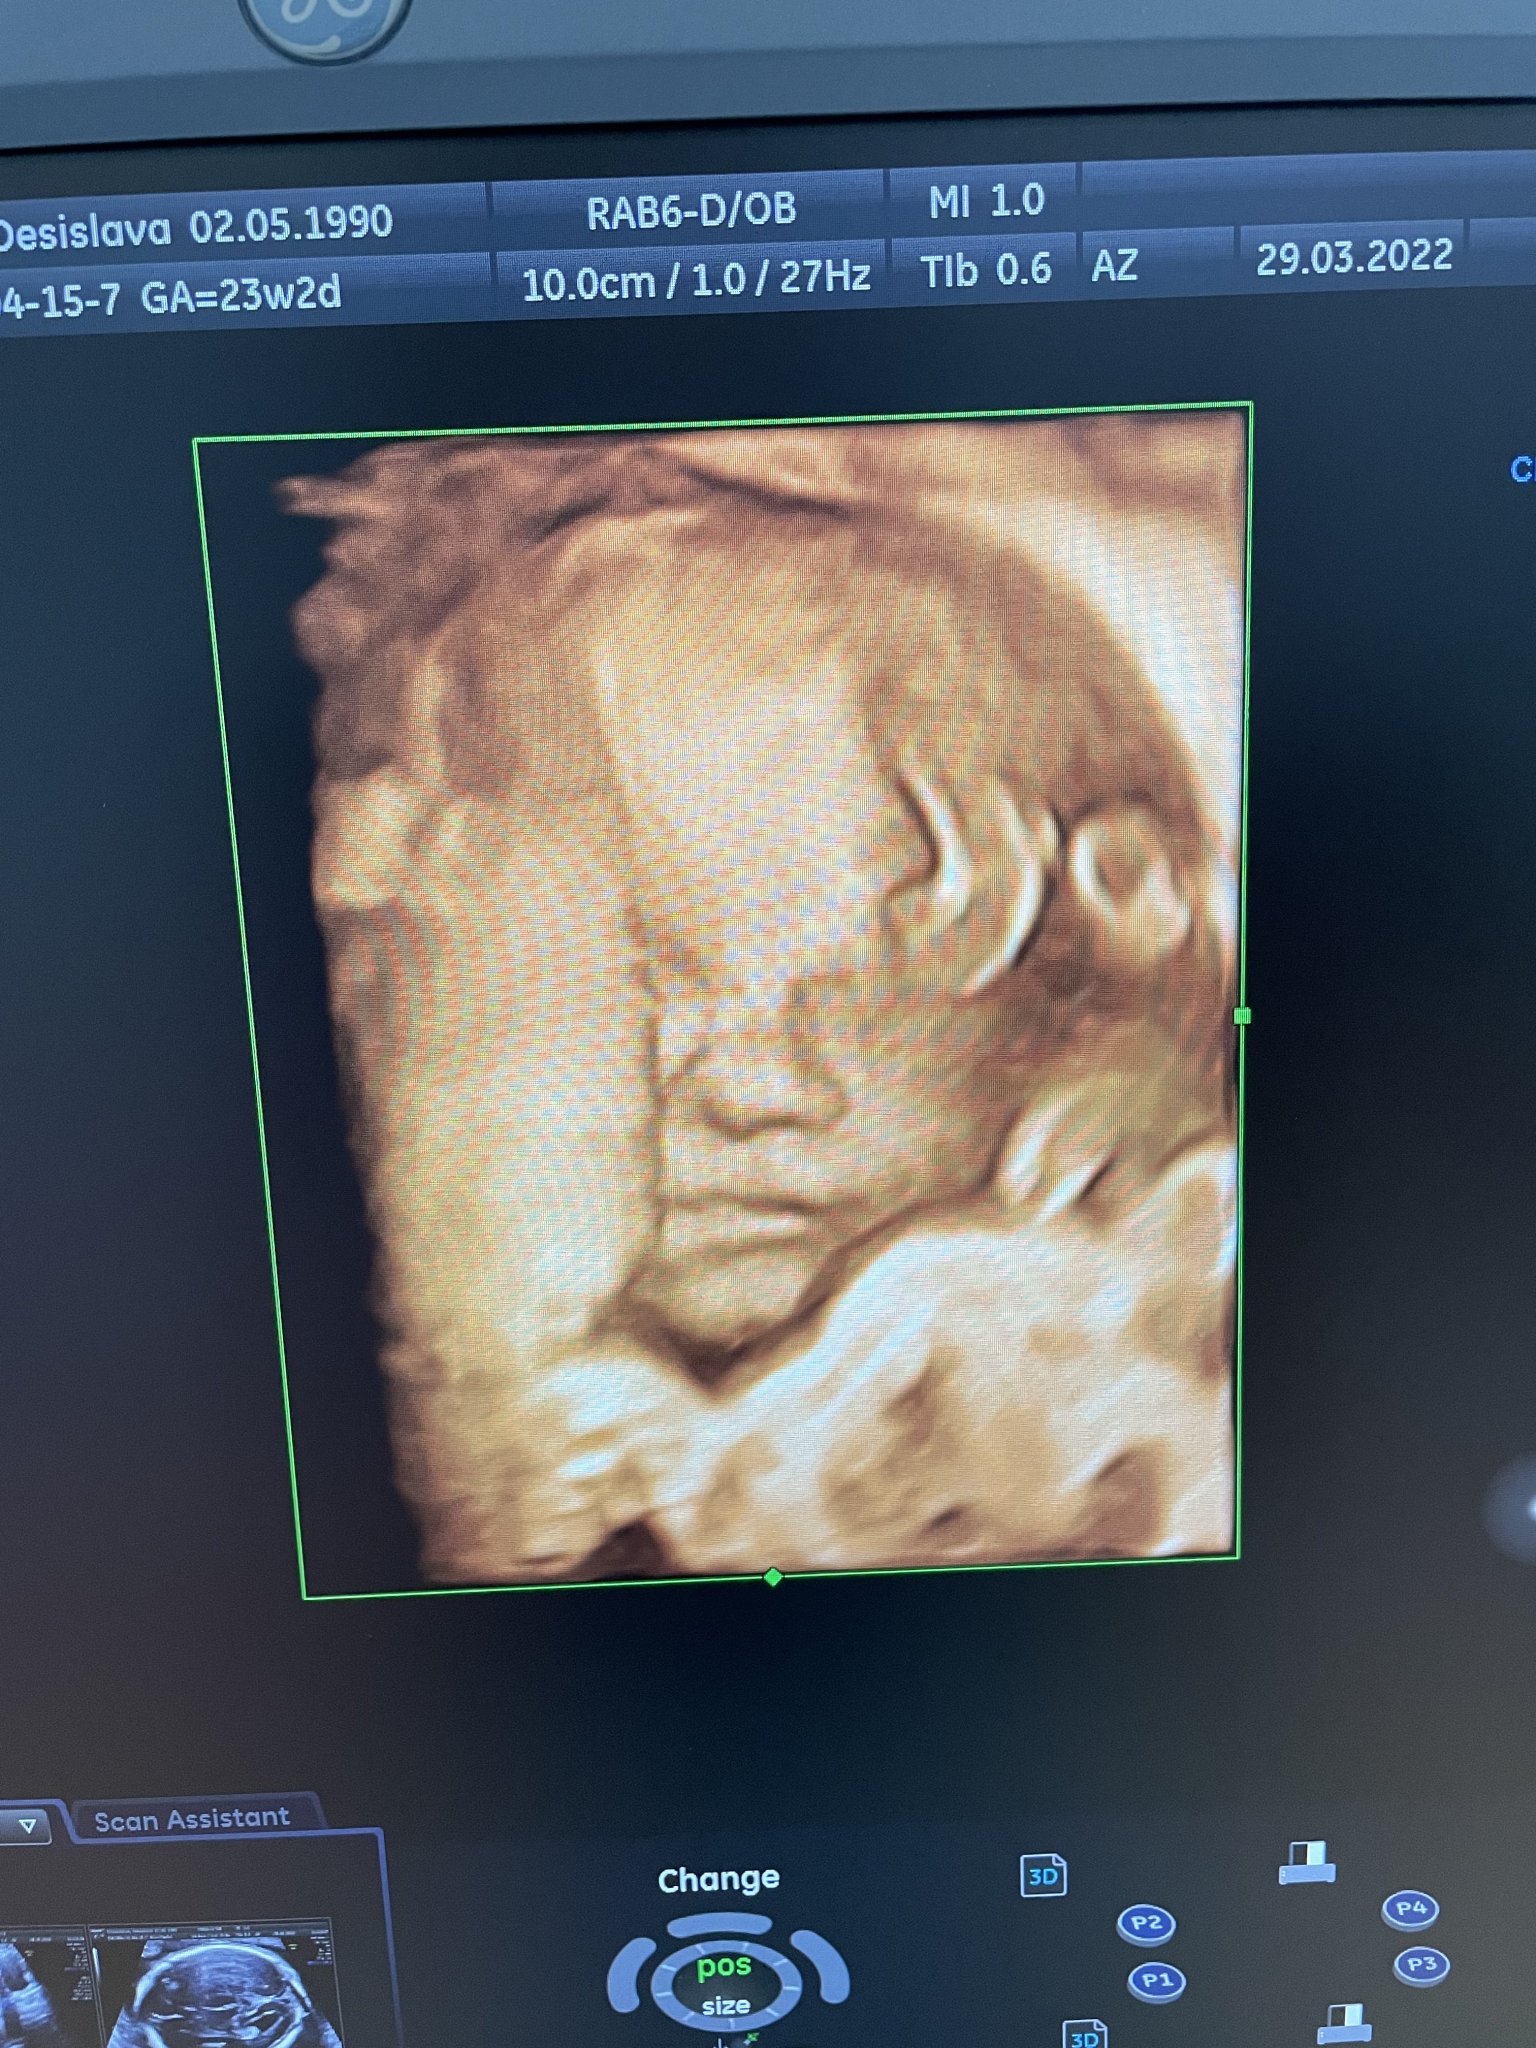

По време на бременност се препоръчват различни изследвания и прегледи, включително фетални морфологии, ехокардиографии, изследвания на хемостaзата, кръвни изследвания за хормони и витамини, както и други тестове за здравето на бебето и майката. Важно е тези прегледи да се извършват под наблюдението на специалисти и сертифицирани лекари, които могат да предоставят подходяща медицинска грижа и консултации.

Какви са препоръките за фетална морфология и изследвания на бебето по време на бременност?

Какво представлява ФМ и защо е важно?